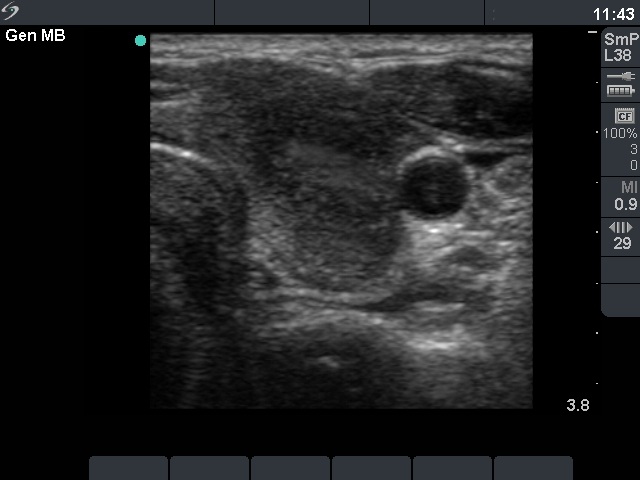

Ultrasonography: diffusely moderately hypoechogenic lobes with several circumscribed, even more hypoechogenic areas with blurred borders.